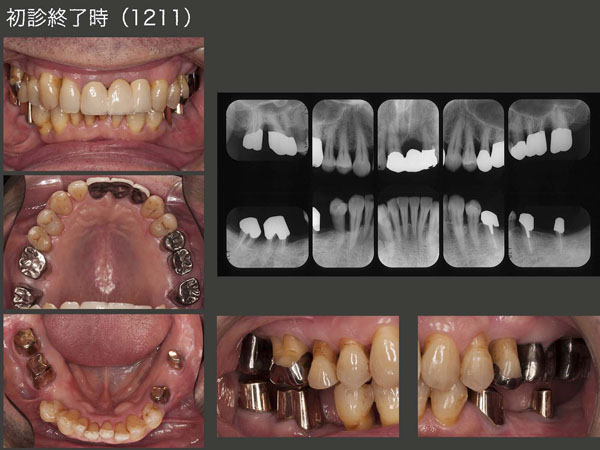

2012年11月,初診終了時の状態.下顎は,片側処理のコーヌス義歯を2つ装着した.支台歯は歯周病罹患歯であったことと,移植歯を用いていることから,将来の変化に対応できる補綴装置にしたい.また根面の清掃が行いやすいことから,可撤式義歯を装着した.

左上1の欠損はブリッジで対応した.左上1は残念ながら抜歯に至ってしまったが,いきなり抜歯するよりも自然挺出したことで骨の高さが確保でき,審美面においては意義があったと思う.

嚙める歯が増えるにつれて,また咬みしめを自覚するようになったとのこと.元々TCHの自覚があったので,今後くれぐれもTCH,咬み過ぎには注意していただくようにとお話しした.

初診終了,コーヌス義歯装着時.左側は移植を行ったことで遊離端欠損が回避できた.左下5と移植歯の2本のみでも対応できるが,将来の保険として左下4へクラスプを付与した設計.右側も健全歯である右下4はクラスプで対応した.